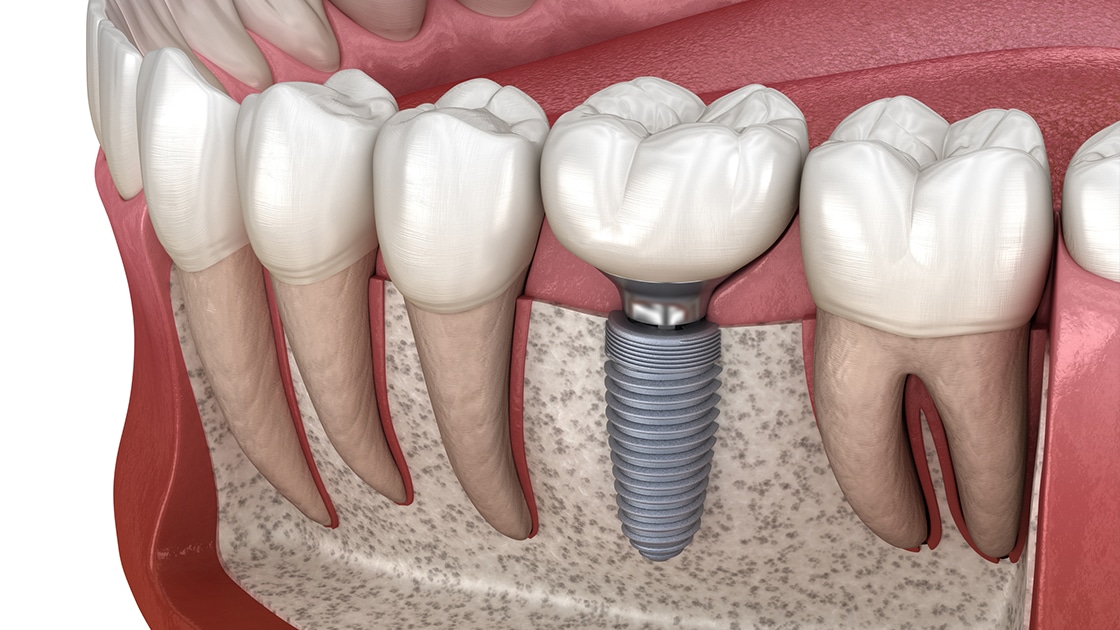

Dental Implants

Dental implants are composed of three pieces: a small screw made of a biocompatible metal called titanium, an abutment that connects the screw, and the final restoration.